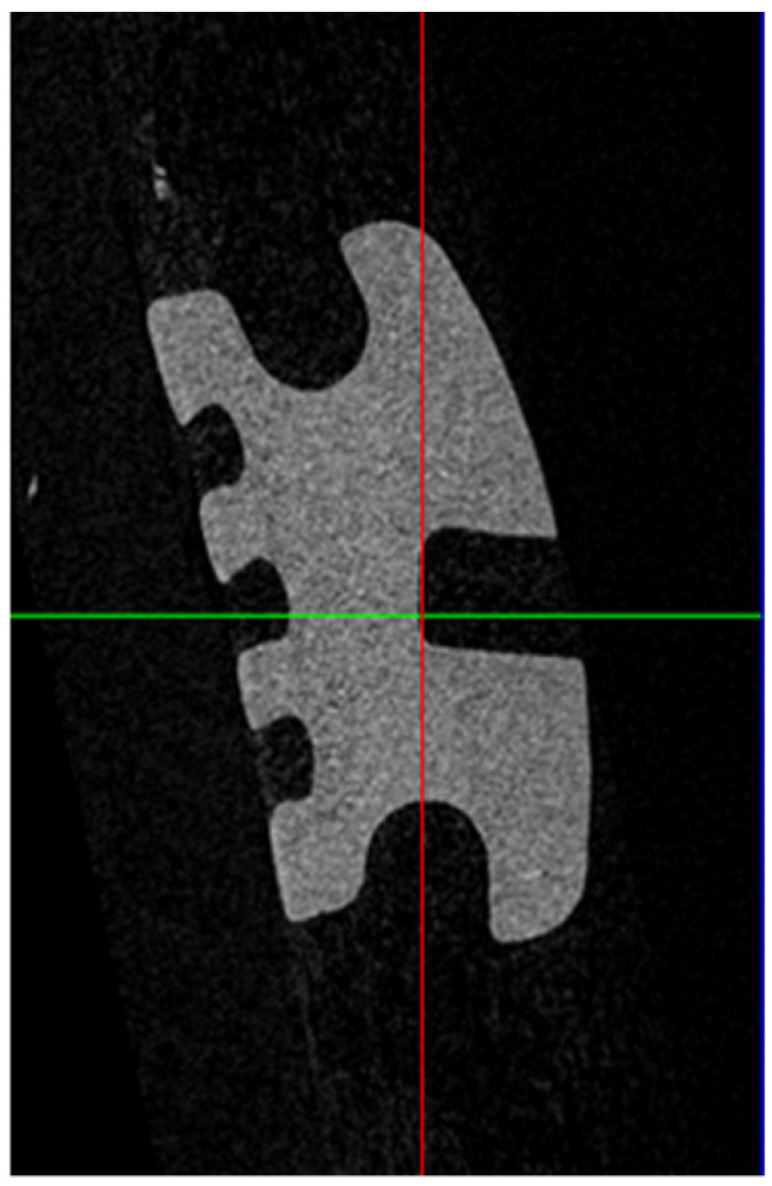

The resultant 4000 voxel three-dimensional images were manipulated using dedicated software (DataViewer; Bruker microCT, Kontich, Belgium) to standardize the orientation of the image. This was achieved by aligning the base of the bracket slot so that it was parallel to the X–Y plane. Two-dimensional images were obtained in the Y–Z plane at the middle of the distal wing slot on each bracket for analysis. They were then processed using dedicated software (CTAn; Bruker microCT, Kontich, Belgium), where images were binarized by thresholding, and, then, saved for further analysis. The images were exported into image-analysis software (Image J; WS Rasband, US National Institutes of Health, MA, USA), so that measurements could be taken (Figure 3).

Figure 3.

Micro-computed tomography (micro-CT) image of a ceramic bracket.

Due to the rounding of bracket slots at their lateral edges, the middle of the distal wing slot on each bracket was selected for measurement. The measurement was taken perpendicular to the slot base. Similarly, since slots can be rounded at the slot entrance and base, the bracket slot height 100 µm from the slot entrance (external height) and 100 µm from the slot base (internal height) were measured (Figure 4). This enabled the evaluation of slot size accuracy as well as whether the height was constant from the entrance of the slot to the base. This measurement method is consistent with the method used in other studies [13,14]. All measurements were rounded to the nearest micron and then, converted to 1/1000th of an inch. The micro-CT scanning and measurements were performed by an experienced investigator (M.A.A).